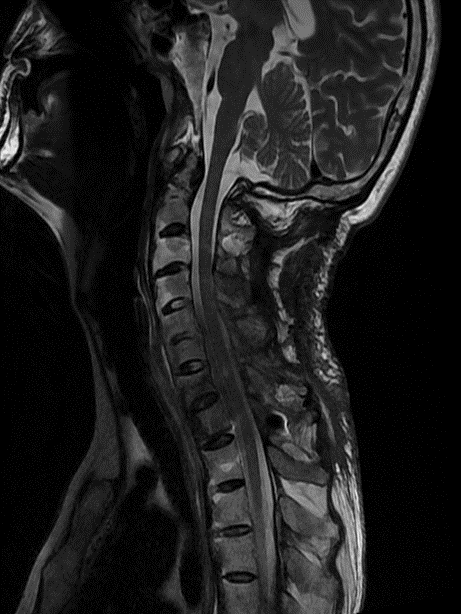

去年,家住昆山的金先生走路的时候不慎摔倒,下颌撞击硬物后感到颈部疼痛难忍,到当地医院查CT显示:(枢椎)齿状突骨折,骨折块向椎管方向移位。齿状突骨折属于上颈椎,位于头颅和颈椎的交界区域,是连接生命中枢的要塞,解剖结构复杂,有椎动脉和中枢神经从中穿过,稍有不慎就会引起大出血、瘫痪、甚至立即死亡。这类手术属于上颈椎手术,曾一度被视为骨科的手术禁区,国内仅有少数医院能够开展这一类手术,一般医师不敢轻易尝试。在业内医师的推荐下,家属送金先生来到了苏州大学附属独墅湖医院,找到了姜为民主任。

接诊后得知,金先生还患有强直性脊柱炎多年,这种疾病直接的后果是脊柱强直如棍棒,骨质变脆易骨折,被冠名以“不死的癌症”。姜主任详细了解金先生的病史后,认为该患者的治疗关键在于以下三个方面:一是脊柱强直,手术部位的位置深难以显露,解剖复杂。二是C2、C3左侧椎弓根发育异常狭小,置入椎弓根螺钉困难。三是齿状突骨折向后方移位明显,通常向前脱位较为常见复位也较容易,此种脱位的复位具有较大的难度和损伤脊髓的风险,对于术者而言是个巨大考验。

金先生伤后第7天,姜主任医师团队在麻醉手术科的密切配合下成功为他实施手术。姜主任凭借多年徒手置钉的过硬技术经验,2小时不到便完成了手术,术中出血仅100ml。术后CT显示齿状突完美复位,螺钉“不偏不倚”的位置恰到好处。术后,金先生在骨科护士长张霞芬护理团队的精心护理下,15天后伤口拆线康复出院。